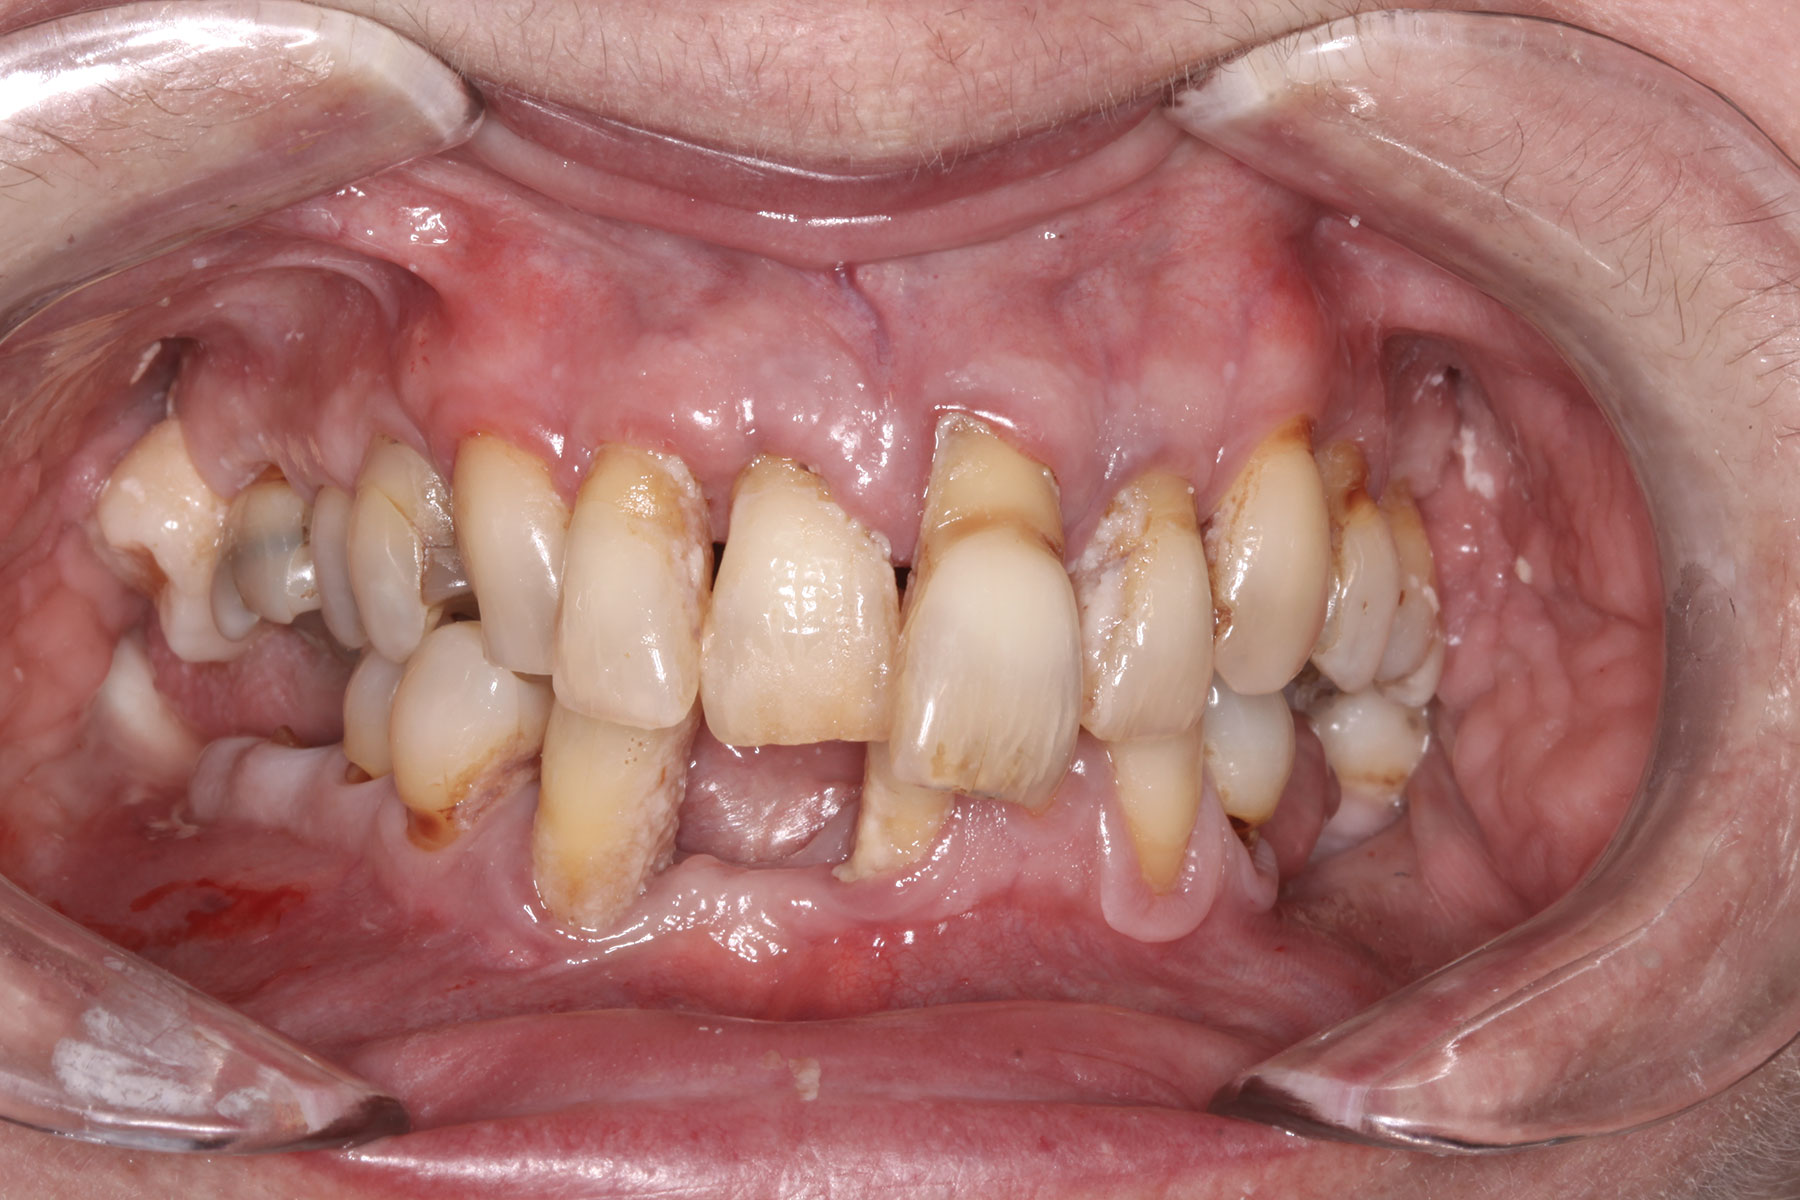

A 36-year-old male patient presented with a highly compromised maxillary dentition comprised of only teeth Nos. 4, 6, 7, 9, 10, 11, and 14 (Figure 1 and Figure 2). This poor condition was the result of only sporadic dental care with extractions and no teeth replacements. Soft tissues had normal contour, and bone profiles were generally sustained and favorable. The patient was excited about having the option to transform his compromised esthetics and function in one visit.

Fig 2. Initial presentation, intraoral view.

Figure 2

Fig 10. Initial clinical situation, intraoral view.

Figure 10

Fig 25. Initial clinical presentation, intraoral view.

Figure 25